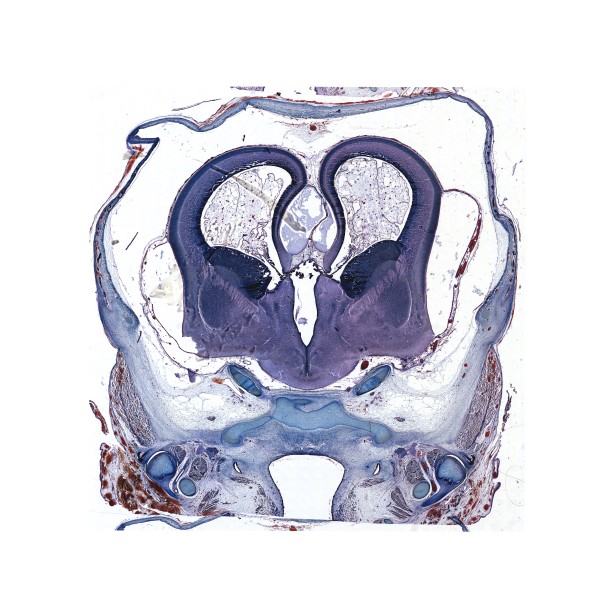

Human brain development atlas

14th gw

Mallory